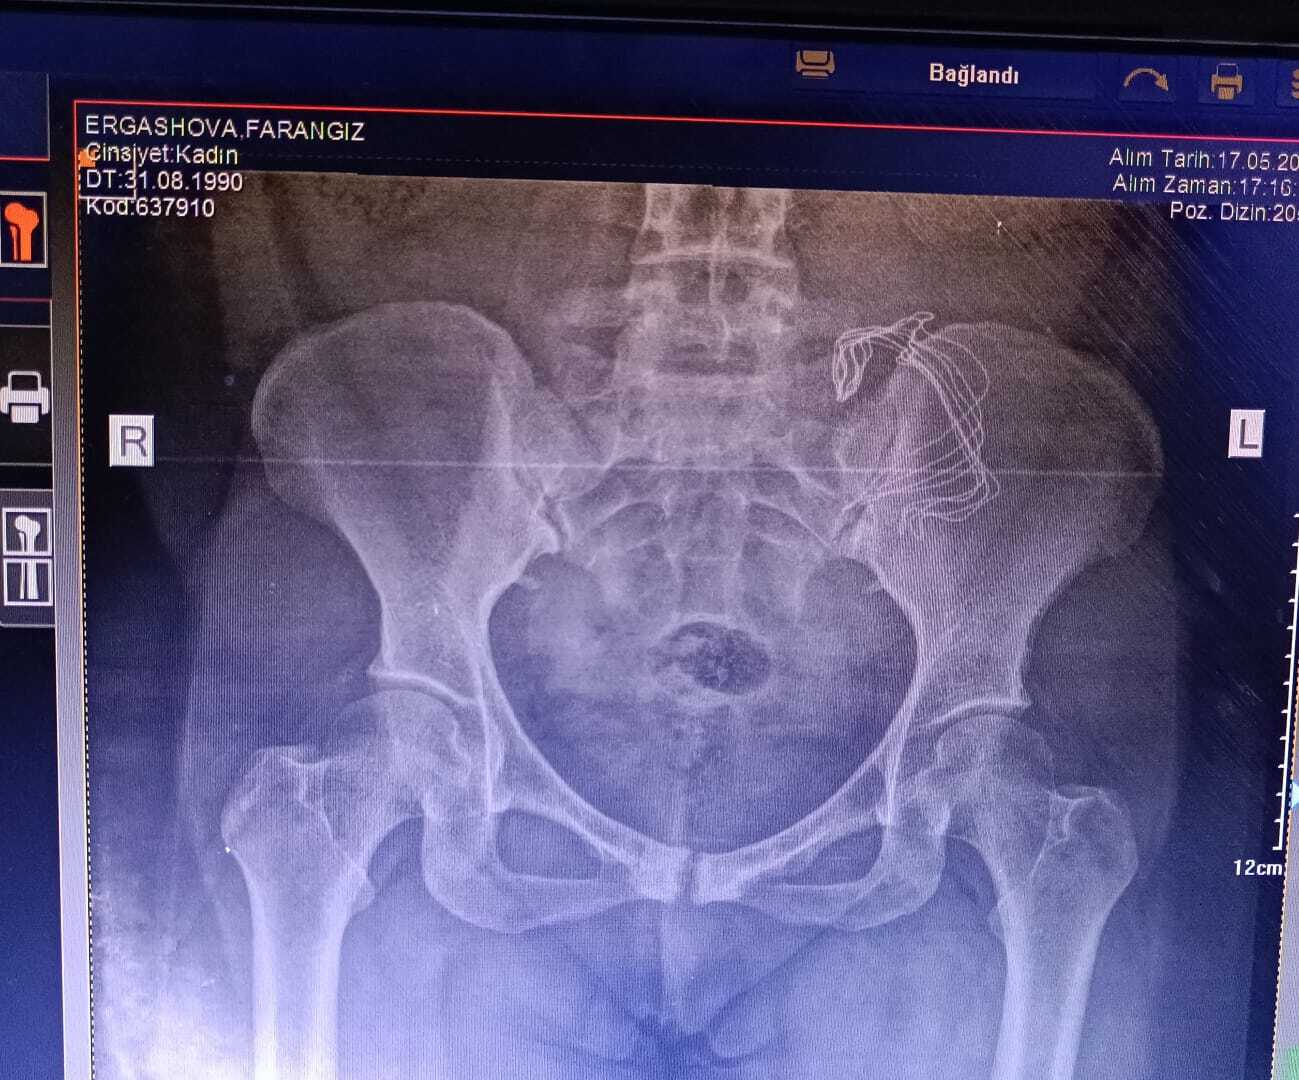

Hastanede çekilen tomografi.

Hastanede yapılan kontrollerde ve çekilen tomografide sonra Frangiz Ergashova ameliyata alındı. Ameliyattan sonra Ergashova’nın karnında doğum sonrası unutulan 15 santimetre büyüklüğünde gazlı bez olduğu ortaya çıktı. Frangiz Ergashova, 10 aydır yaşadığı ağrılara ihmalin neden olduğunu öğrendi. Umut Can ismini verdikleri oğlunun doğumdan sonra 12 gün boyunca küvezde kaldığını söyleyen aile, durumunun şu an iyi olduğunu belirterek hastaneden ve doktordan şikayetçi oldu.